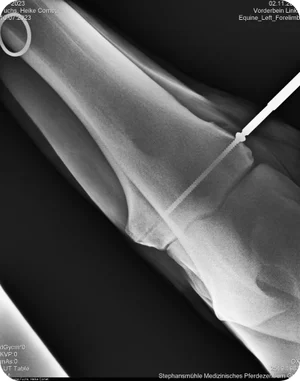

A radiographic examination revealed a bone cyst in the LF elbow.

Comet received surgical treatment of a subchondral lucency using a bone screw.